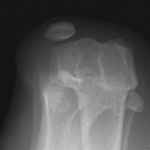

La luxation de la rotule résulte occasionnellement d’une lésion traumatique du genou, provoquant une boiterie sévère soudaine du membre. Cependant, la cause précise reste incertaine chez la majorité des chiens mais est probablement multifactorielle. La rainure fémorale dans laquelle se trouve normalement la rotule est généralement peu profonde (Figure 2a, Figure 2b) ou absente chez les chiens présentant une luxation patellaire non traumatique. Le diagnostic précoce de la maladie bilatérale en l’absence de traumatisme et la prédisposition de la race soutiennent le concept que la luxation patellaire résulte d’un désalignement congénital ou développemental de l’ensemble du mécanisme de l’extenseur. La luxation patellaire développementale n’est donc plus considérée comme une maladie isolée du genou, mais plutôt comme une conséquence d’une anomalie squelettique complexe affectant l’alignement global du membre, incluant:

Fig. 2a Vue pré-opératoire par radiographie du genou: la rainure fémorale est peu profonde avec la rotule à l’extérieur de sa rainure.